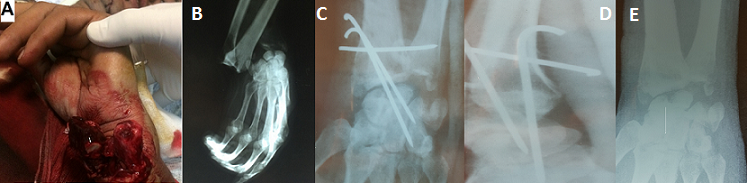

La luxation radio carpienne est rare, sa fréquence est de 0,2% des luxations. La forme pure reste une entité exceptionnelle. Nous rapportons une observation typique de cette lésion. Il s'agit d'un patient âgé de 32 ans, victime d'un accident de la voie public. Admis aux urgences ou un examen du membre supérieur gauche a objectivé une plaie transversale en regard de la face palmaire du poignet gauche (A), l'examen vasculo-nerveux est sans particularités. Une radiographie du poignet gauche face et profil a mis en évidence une luxation postérieure pure radio carpienne gauche (B). Le patient a été opéré 2 heures après le traumatisme au bloc opératoire, sous anesthésie locorégionale. Après la réduction de la luxation radio carpienne le patient a bénéficié d'un embrochage radio-lunaire et radio-scaphoidienne puis un embrochage transversale radio-lunaire. La radiographie de contrôle a confirmé la réduction de la luxation (C, D). Le patient a bénéficié d'une immobilisation du poignet pendant 6 semaines, suivie d'une ablation de broches (E) puis des séances de rééducation. Après un recul de 18 mois, l'évolution était bien, avec une mobilité normale du poignet.